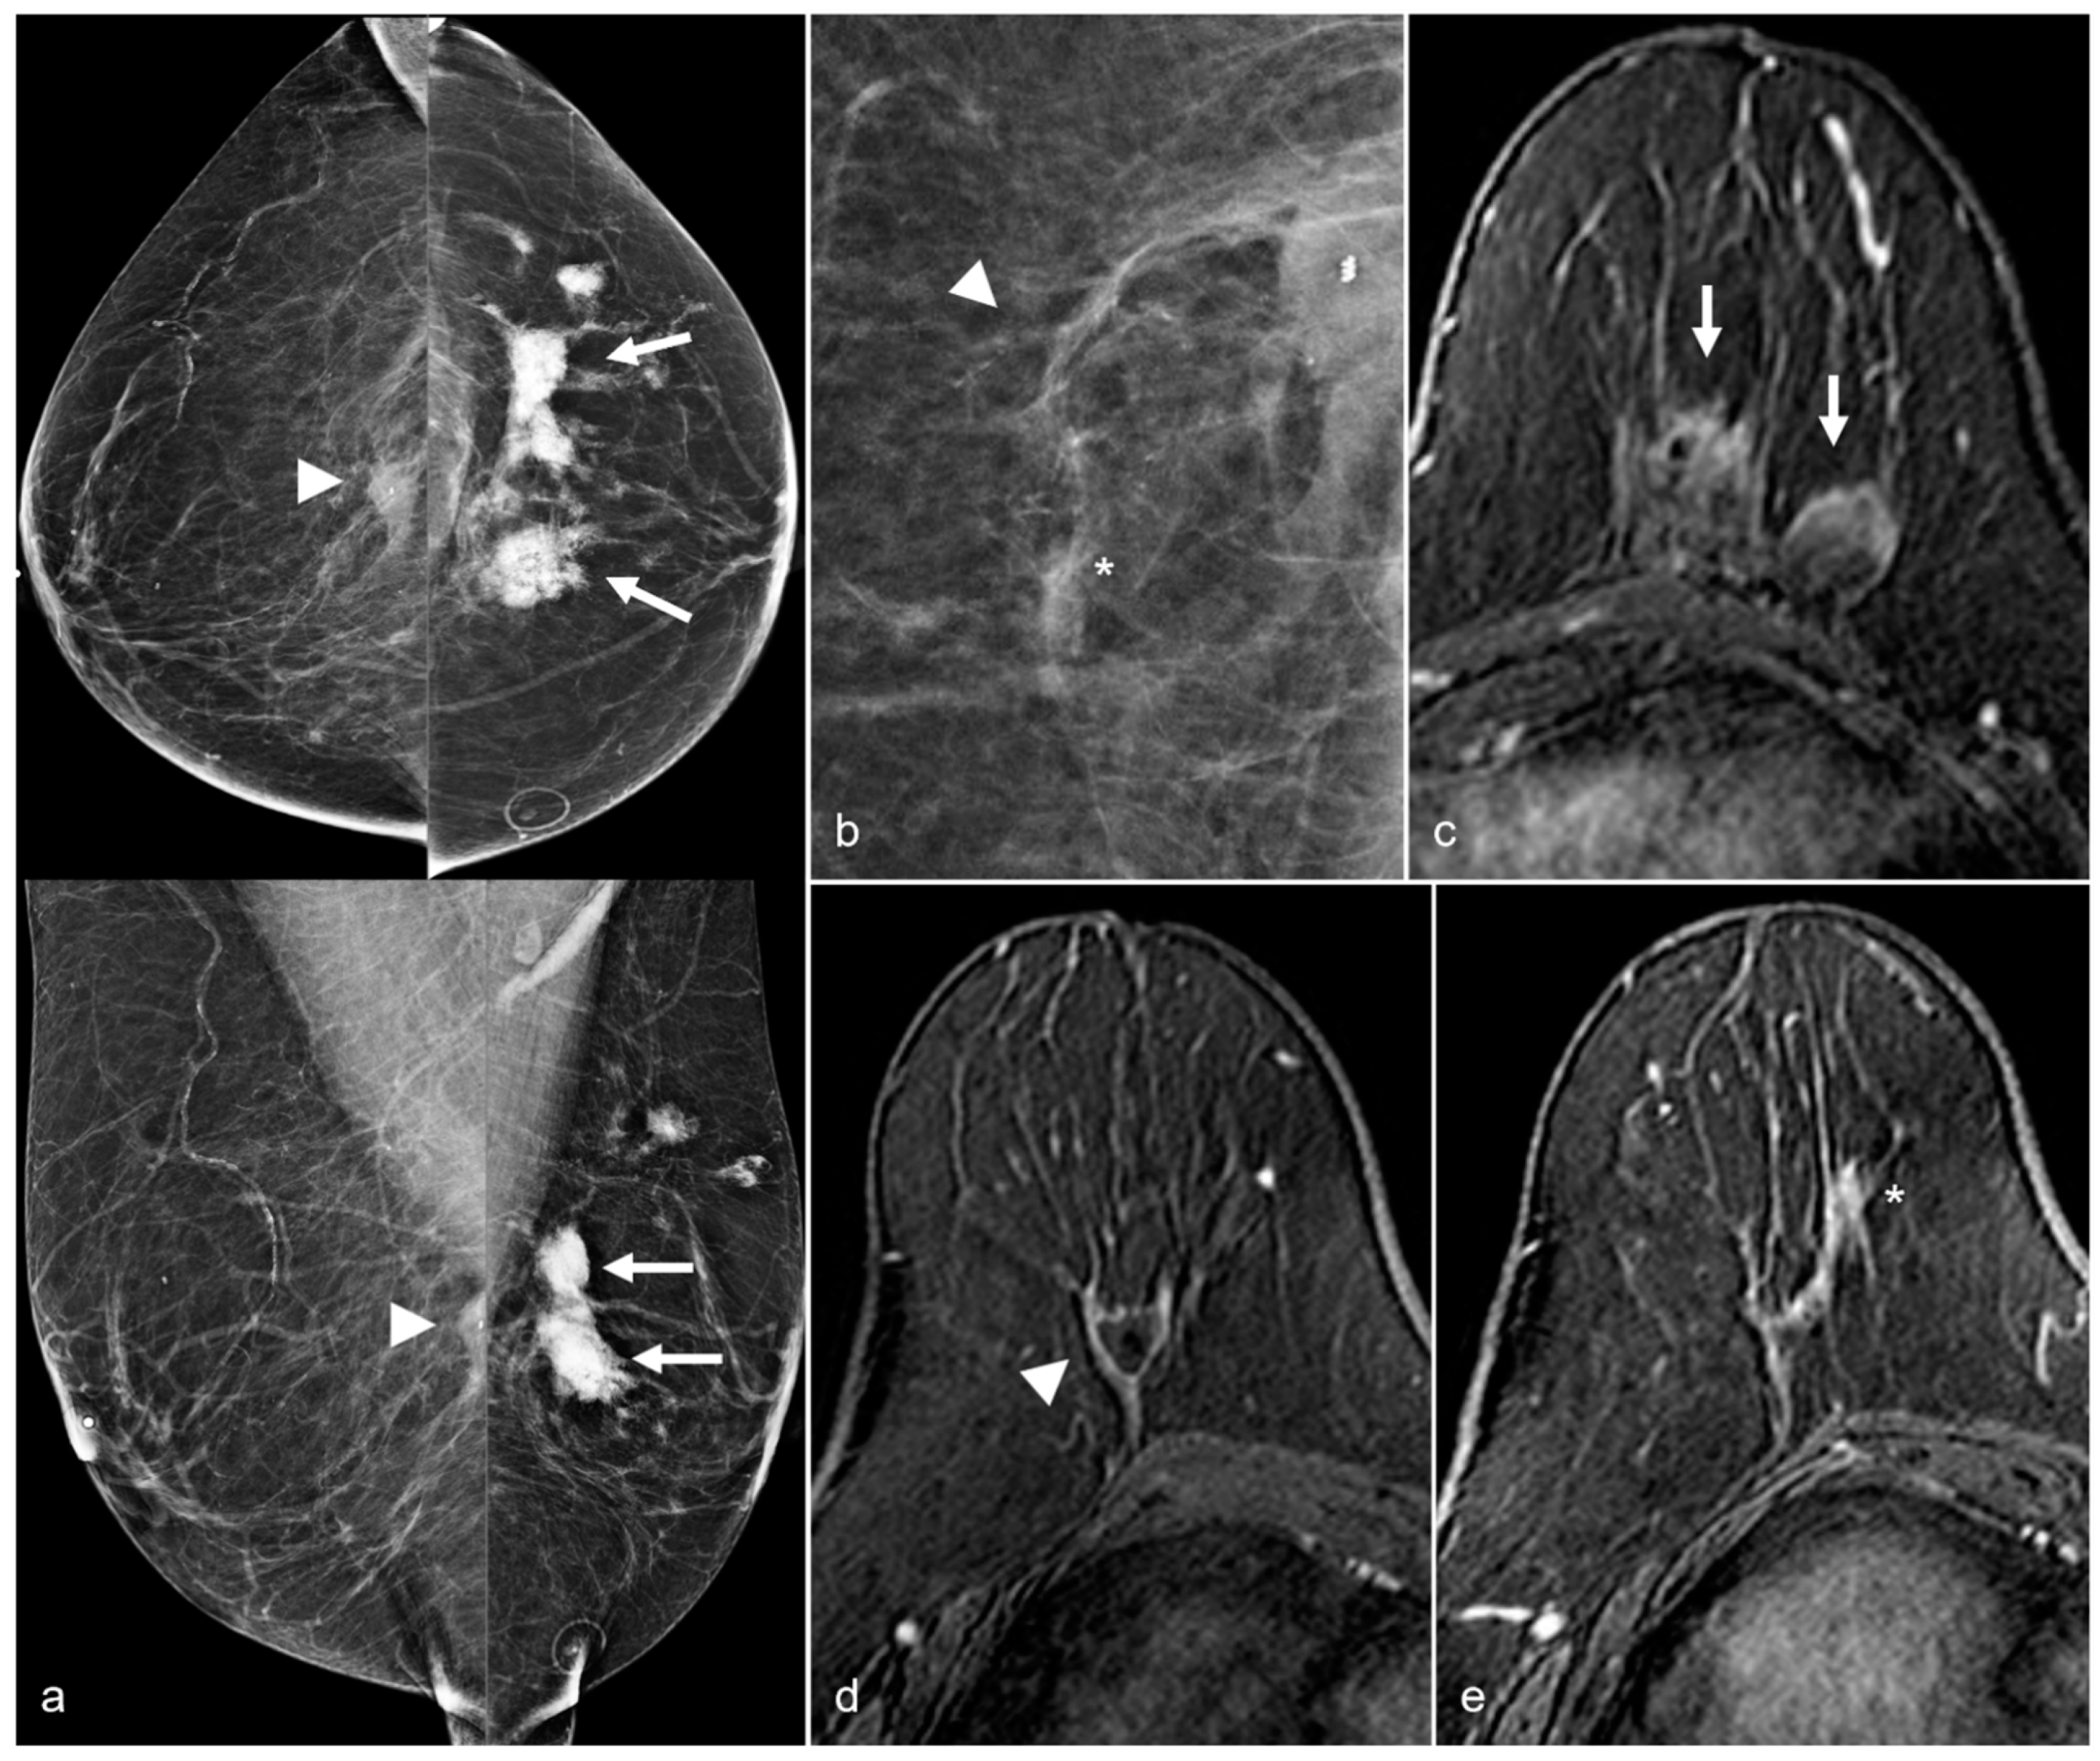

Figure 17. A 50-year-old woman with a history of subglandular silicone implants, status post BES. Screening mammograms with bilateral CC (a) and MLO views (b) demonstrate a mass in the left breast upper outer quadrant (arrowhead). BES changes are more prominent in the right breast with focal asymmetries in the prepectoral region (arrows) with dystrophic calcifications. Subsequent ultrasound examination of the left breast in the transverse plane (c) with ultrasound-guided biopsy revealed triple-negative invasive ductal carcinoma. T1-weighted post-contrast MRI (d) revealed a left breast enhancing mass (arrowhead) with a biopsy clip. There was also right greater than left prepectoral fluid (arrows) on the axial T2-weighted images (e).